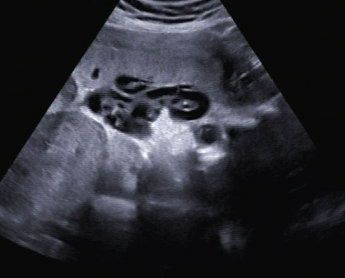

Ein zunächst durchgeführtes CTG war unauffällig. Im Rahmen der sonografischen Untersuchung zeigte sich der Fötus soweit beurteilbar zeitgerecht entwickelt. Dennoch konnte ein Anhydramnion festgestellt werden(Abb. 1, 2), weshalb auch kein fetales Gesicht darstellbar war (Abb. 3).

Im Abdomen war die Blase nicht gefüllt darstellbar (Abb. 4).